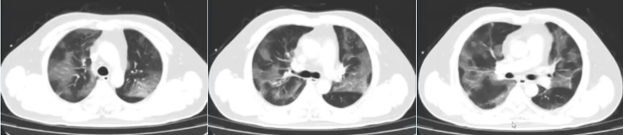

4月12日胸部X线片可见患者肺部病灶较前吸收(图2),CT值逐渐升高(27.4→30.6→33.2)。

图2  患者拔管前胸片变化

拔管后胸部CT可见斑片样渗出明显改善(图3),PaO2升高,氧合改善。

图3  患者拔管后复查胸部CT(4月13日)